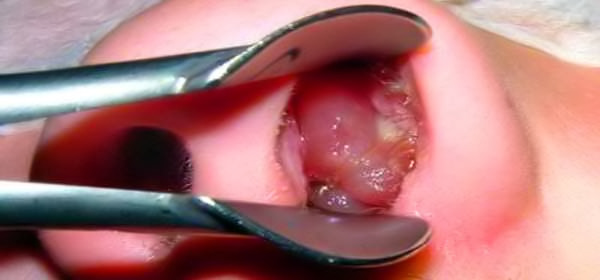

Zabieg operacyjny usunięcia

polipów jest jedynie leczeniem skutków zapalenia i w dużej mierze

wyrazem naszej bezsilności wobec tej choroby.